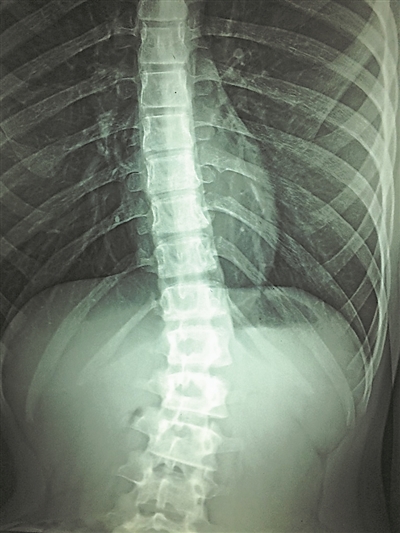

图为受损伤的脊髓。图片来源:物理学家组织网